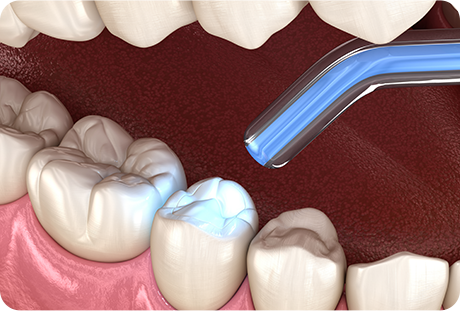

むし歯部分を削り取り、穴の部分に保険適用の白いコンポジットレジンと呼ばれる合成樹脂を詰めていきます。 型取りが必要なく、その日のうちに治療が終わります。